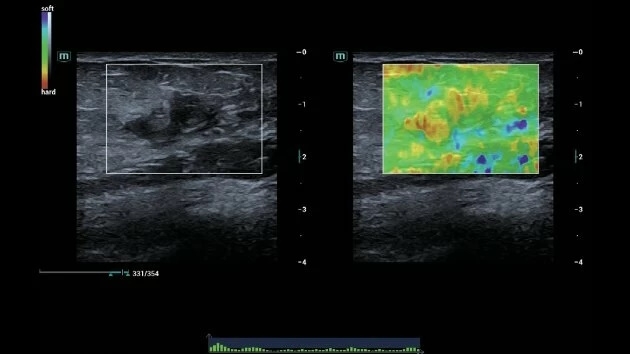

• Звуковая сенсорная эластография (STE) для точной оценки жесткости тканей